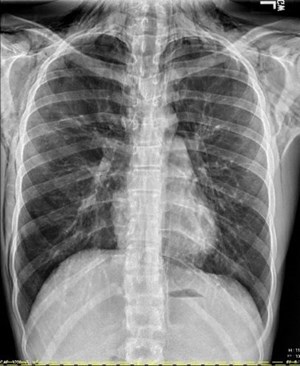

2nd Place Emage Winner: Fibrosing Mediastinitis

2nd Place Emage Winner: Cardiomyopathy